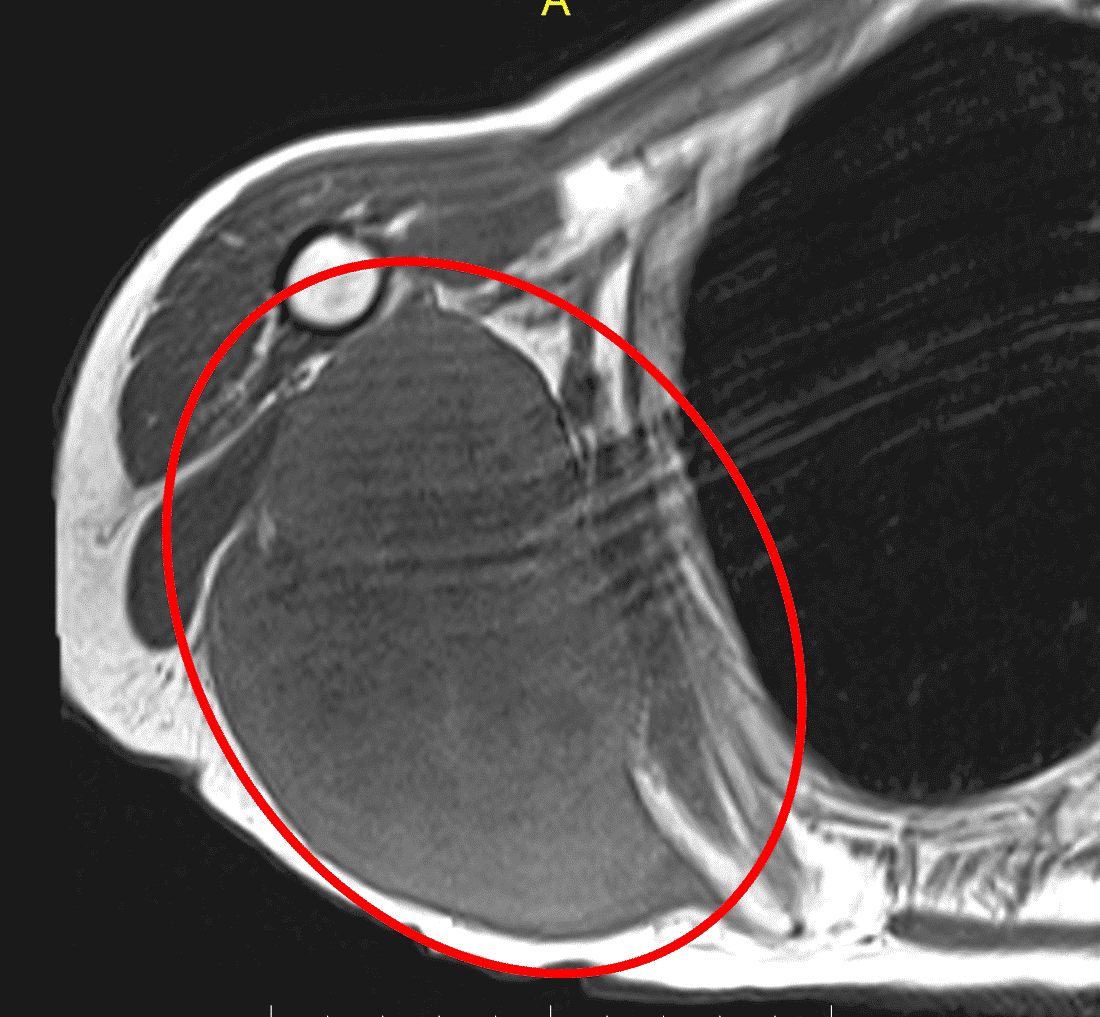

Адекватне обстеження перед будь-яким лікуванням або хірургічним втручанням є надзвичайно важливим. Магнітно-резонансну томографію (МРТ) з контрастом і без контрасту слід розглядати при всіх утвореннях м’яких тканин, які збільшуються або перевищують 4 см. Якщо візуалізація, отримана до направлення, є незадовільною, лікарю слід без вагань повторити або отримати додаткову візуалізацію, щоб адекватно побачити пухлину. В Т1 режимі МРТ якісно візуалізуються доброякісні жирові пухлини, такі як ліпоми або жирові пухлини низького ступеня злоякісності, такі як атипові ліпоматозні пухлини (АЛП), особливо якщо такі пухлини добре окреслені, доволі однорідні та з внутрішнім сигналом, подібним до внутрішнього сигналу від нормальної жирової тканини (зобр. 1).

Зобр. 1: (A) МРТ, фаза T1, що показує доброякісну ліпому правого підгрудного відділу, підтверджену наступною резекцією. Вона за внутрішньою структурою однорідна і з таким самим сигналом, як і від сусідніх жирових тканин.

Зобр. 1: (B) МРТ, фаза Т1, верхня ділянка правого стегна, що демонструє атипову ліпоматозну пухлину, яка дещо більш невиразна з більш складною внутрішньою структурою в порівнянні до навколишньої нормальної жирової тканини.